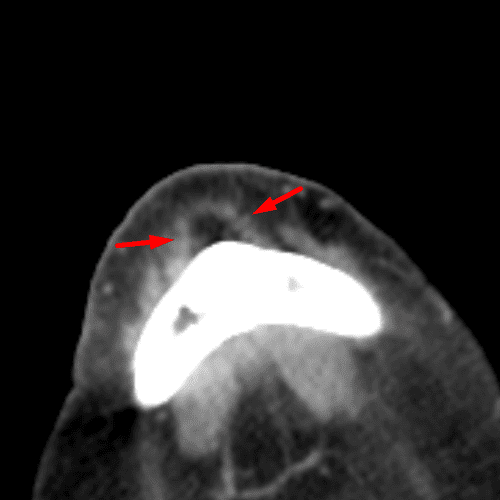

Calcific Scleral Plaques

Case 21